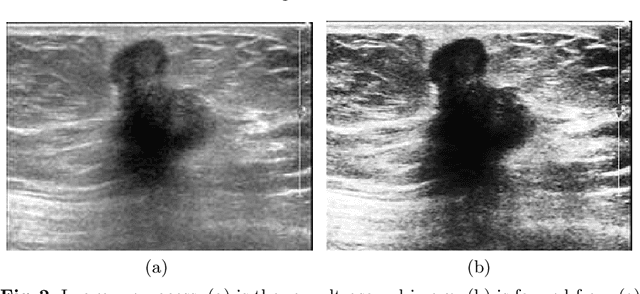

Abstract:Ultrasound image diagnosis of breast tumors has been widely used in recent years. However, there are some problems of it, for instance, poor quality, intense noise and uneven echo distribution, which has created a huge obstacle to diagnosis. To overcome these problems, we propose a novel method, a breast cancer classification with ultrasound images based on SLIC (BCCUI). We first utilize the Region of Interest (ROI) extraction based on Simple Linear Iterative Clustering (SLIC) algorithm and region growing algorithm to extract the ROI at the super-pixel level. Next, the features of ROI are extracted. Furthermore, the Support Vector Machine (SVM) classifier is applied. The calculation states that the accuracy of this segment algorithm is up to 88.00% and the sensitivity of the algorithm is up to 92.05%, which proves that the classifier presents in this paper has certain research meaning and applied worthiness.